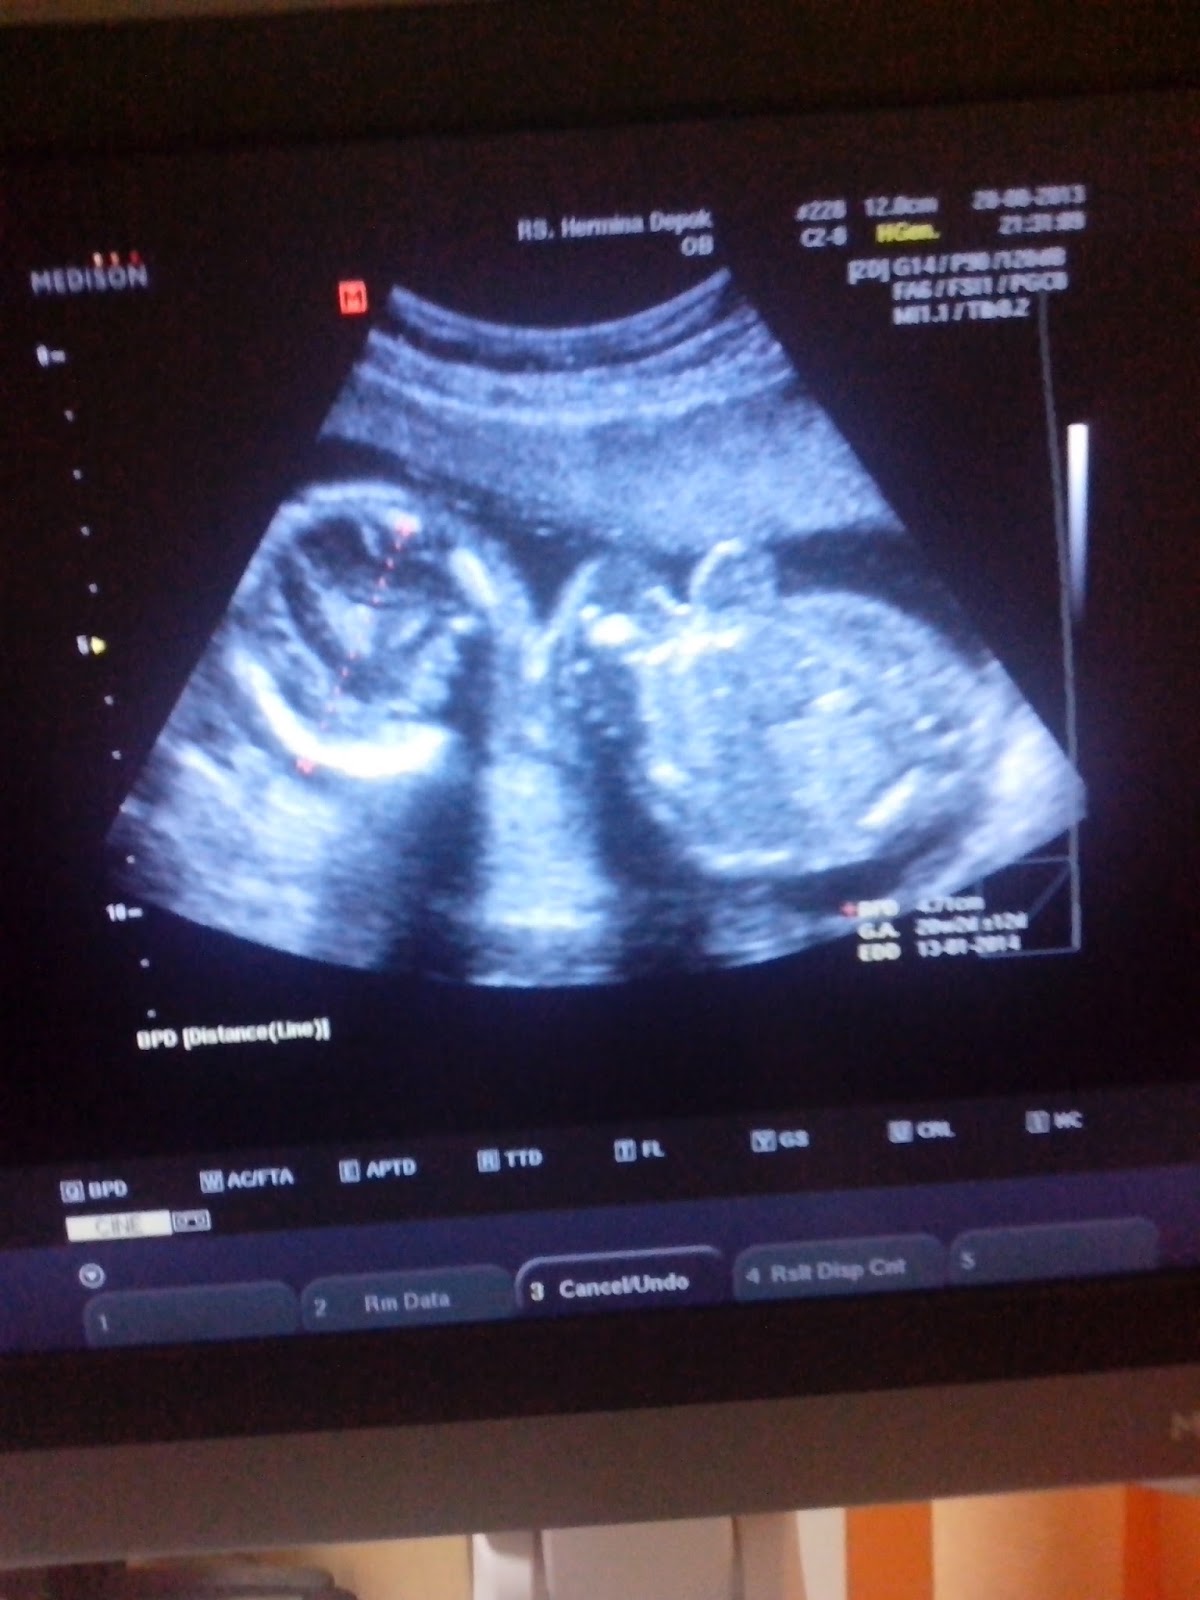

Minggu ini usia kandunganku memasuki usia 20 minggu, artinya jenis kelamin dede bayi sudah bisa terlihat yeay.. sudah ngga sabar nih.. du du du du sambil menunggu antrian dokter, menebak-nebak dalam hati, apa ya kira-kira jenis kelamin dede bayi? mmm.. bagi saya apa aja yang penting sehat dan sempurna.. dan lebih sempurna lagi kalo dede bayi berjenis kelamin perempuan, jadi sepasang deh.. harapan suami saya juga sama, semoga dede bayinya perempuan jadi Keenan punya adik perempuan hehe pasti cantik seperti mamanya hehe.. aamiin.

20 weeks ultrasound

tara.. akhirnya kami mengetahui jenis kalamin dede bayi.. semoga sehat selalu ya sayang.. aamiin.